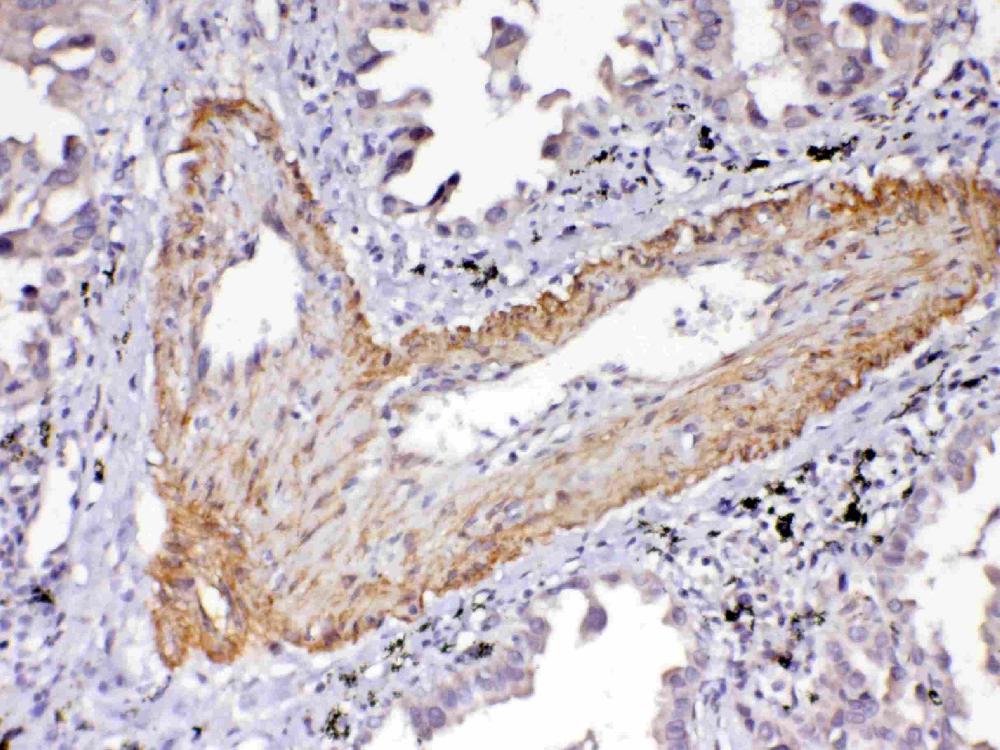

IHC analysis of VEGFR2/KDR using anti-VEGFR2/KDR antibody (A00901-2).

VEGFR2/KDR was detected in a paraffin-embedded section of human lung cancer tissue. Biotinylated goat anti-rabbit IgG was used as secondary antibody. The tissue section was incubated with rabbit anti-VEGFR2/KDR Antibody (A00901-2) at a dilution of 1:200 and developed using Strepavidin-Biotin-Complex (SABC) (Catalog # SA1022) with DAB (Catalog # AR1027) as the chromogen.